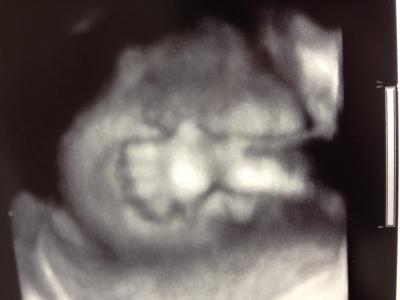

Hey Mädels, war heute beim FA! 8 Uhr ging es los und ich durfte diese dickflüssige, extrem süße Zuckerwassermasse trinken Erst war alles in Ordnung aber nach 20 Minuten hab ich es total mit'n Kreislauf bekommen & hatte das Gefühl mich übergeben zu müssen! Da war es dann auch schon passiert und ich lage die restlichen Minuten auf der Liege. Danach wurde mir noch Blut abgenommen, aber die Ergebnisse sind leider erst morgen da! Danach hatte ich auch noch die Untersuchung Letztes mal konnte ja nur der FA sehen das es ein Junge wird, aber dieses mal war ich mir auch 100 pro sicher! Der kleine Mann wiegt 600 g & ist 29 cm groß Mein kleiner Prachtkerl hat mir sein ganzen Stolz in die Kamera gezeigt Er ist super aktiv und liegt noch ganz tief in mir drin, deswegen mein kleiner Bauch! Dadurch kann ich ja auch nicht mehr soviel essen weil er das ja alles wegdrückt und auf Klo muss ich auch so oft gehen, weil er die Blase gerne als Trampolin benutzt... Ah und Hallöchen 25 ssw

Bild zu Zurück vom FA inkl. Zuckertest - Forum für November - Mamis

Süßes Bild!! Hoffentlich ist alles in Ordnung mit dem Blut!!!